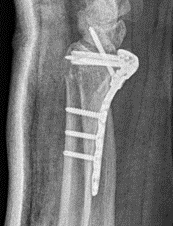

Fragment specific plates

| Volar locking plates | Volar rim plates | Radial styloid plates |

Locking screws act as fixed angle devices Variable angle screws |

Supplementary radial column fixation |

Volar locking plate technique

- apply volar plate with screw fixation in scaphoid and lunate fragments

- +/- radial styloid plate if required